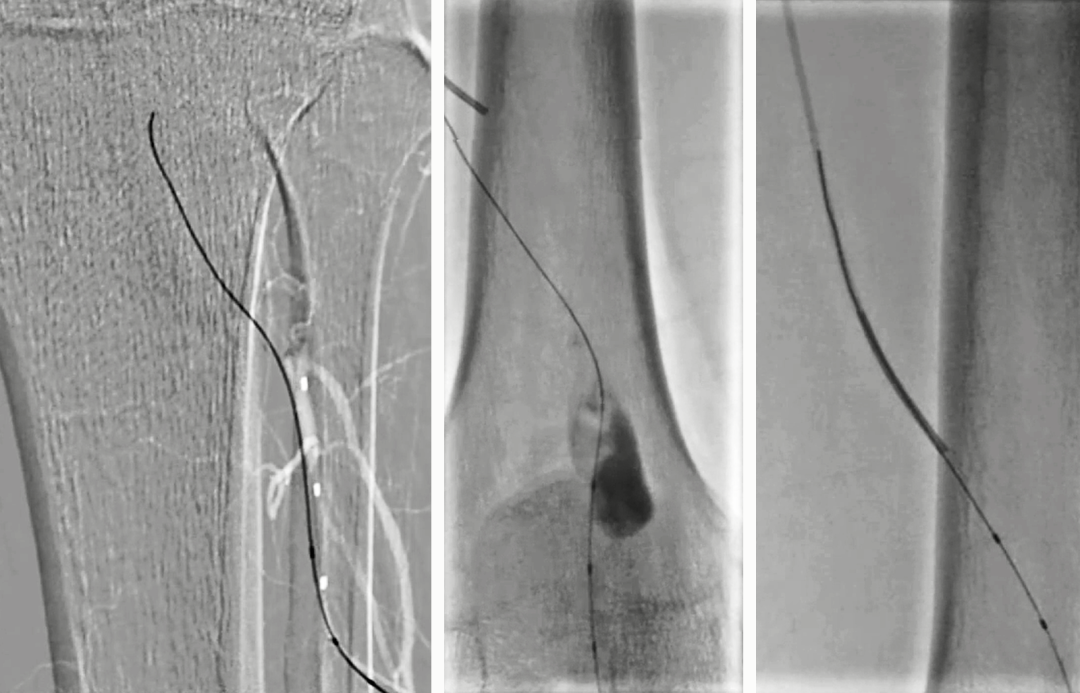

7. 造影发现腘动脉末端1cm可作为覆膜支架远端锚定区;自腘动脉末端至P1段置入5mm×100mm Viabahn;序贯置入7mm×100mm和7mm×50mm Viabahn,近端至内收肌管口水平,覆盖一个侧枝;6mm×200mm球囊后扩;

8.造影见动脉瘤消失、支架通畅、腘动脉远端狭窄和造影剂滞留;自近端将导丝置入腓动脉,3mm×60mm球囊扩张;造影见腓动脉形态良好,无造影剂滞留,见胫前动脉开口狭窄;

9. 入胫前动脉,3mm×60mm球囊扩张;由于脉管炎血管扩张后发生痉挛,予罂粟碱10mg后,胫前动脉和腓动脉近中段血流通畅,但仍存少量痉挛后狭窄,远端流出道通畅;

10. Perclose闭合穿刺点,术毕。

术后第2天患者左下肢皮温改善、花斑消失、可下地行走。

18个月彩超提示左股浅动脉至腘动脉覆膜支架通畅,腓动脉通畅。